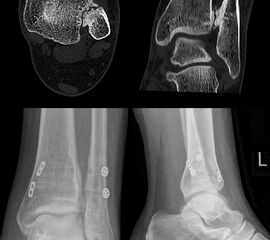

Computertomographie (CT)

Die CT-Diagnostik erlaubt eine kritischere Beurteilung des DTFG. Die Wertigkeit zur Beurteilung von Syndesmosenverletzungen wurde in diversen Studien untersucht. Die Kongruenz im distalen Tibiofibulargelenk sollte in den axialen Schichten beurteilt werden 39. Aufgrund der hohen physiologischen Varianz, ist ein Seitenvergleich empfehlenswert (Abb. 5). So können die anteroposteriore Translation, Rotation und Verkürzung des betroffenen DTFG im Vergleich zum gesunden DTFG verglichen werden 40.